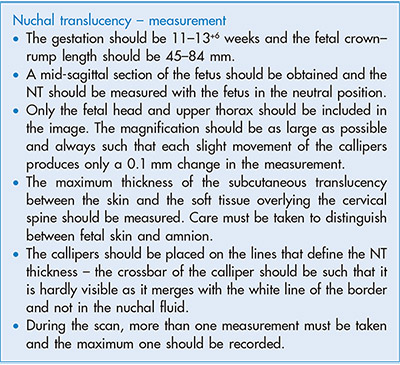

U periodu od 11. do 14. GN procenjuje se rizik od hromozomopatija. U predelu iza vrata bebe pojavljuje se nakupina fluida – nuhalna translucenca (NT). Pojava hromozomskih anomalija povezana je sa dimenzijom ove strukture.

Ukoliko je NT oko 3mm i više, rizik za hromozomsku bolest je veći.

U ovom periodu pregleda se anatomija ploda koja sadrži: kranijum, moždane strukture, nosnu kost, srčanu radnja, želudac, inserciju pupčanika, ruke, noge, protok kroz duktus venosus.

merenje nuhalne trahclucence i double test (free beta hCG+ PAPP-A)